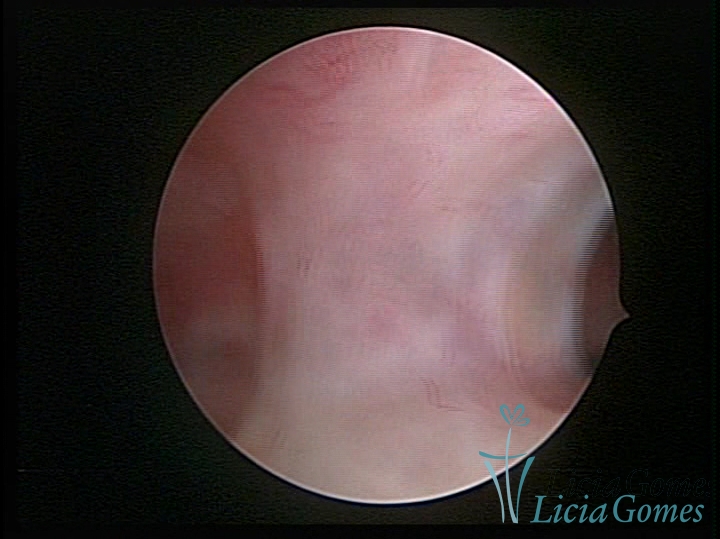

SINÉQUIA TIPO MUCOSA